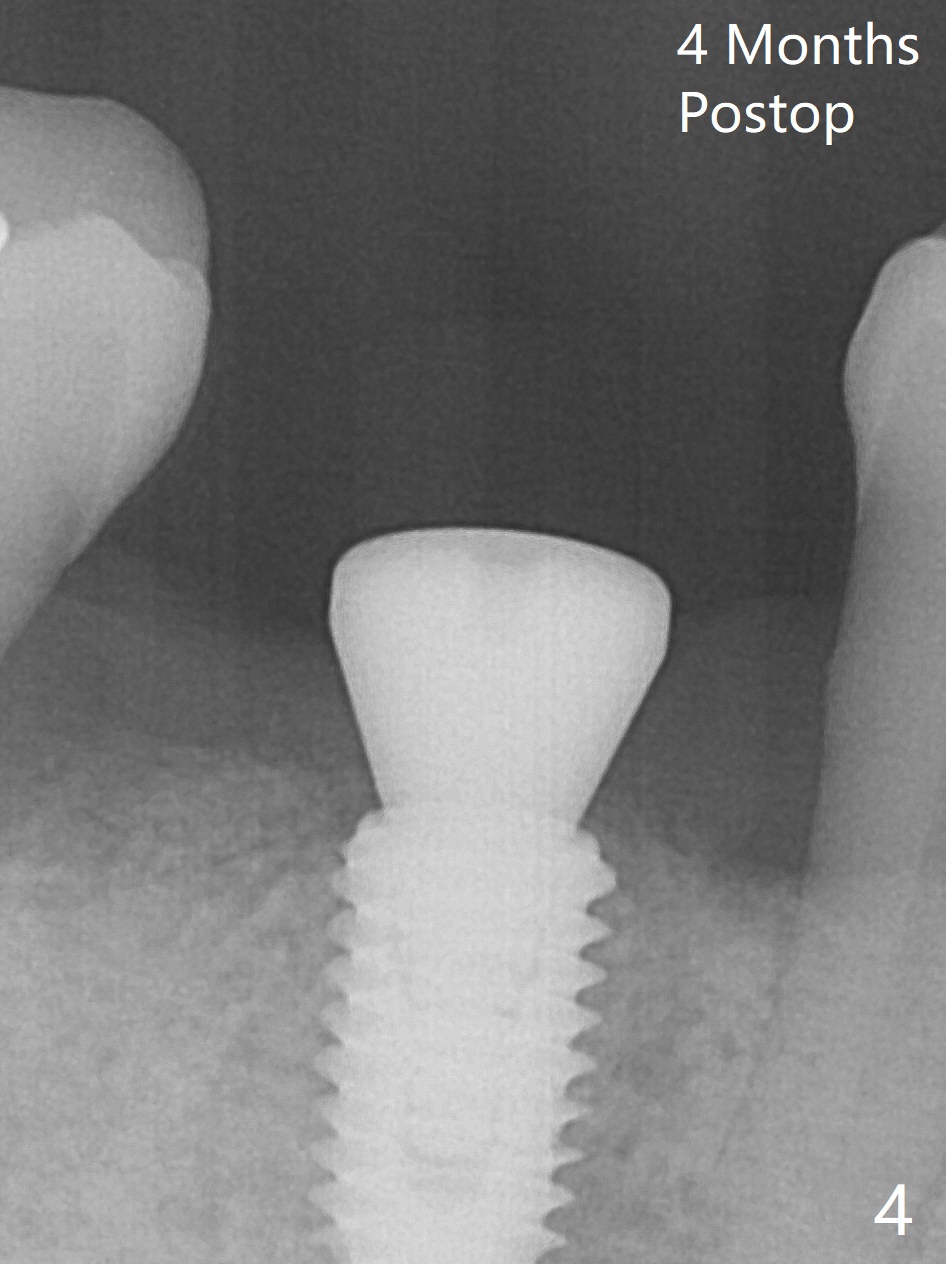

There are two questions before guided surgery at #30.  First, is implant placement 3 months post socket preservation too early?  Will the periapical radiolucency between #29 and #30 affect osteointegration?  Reanalysis of CT >2 months post socket preservation reveals that the lamina dura of the tooth #29 is apparently intact (Fig.1).  Immediately preop clinical exam shows no active infection.  The patient is reluctant to accept RCT at #29.  A 5x10 mm implant is placed slightly subcrestal buccally (which is the lowest, Fig.2).  Immediately postop CT (5x5cm field of view) demonstrates that the implant is covered by graft bone (Fig.3 *) buccally (B).  In fact the autogenous bone harvested from osteotomy is inserted between the 6x4 mm healing abutment and the buccal gingiva.